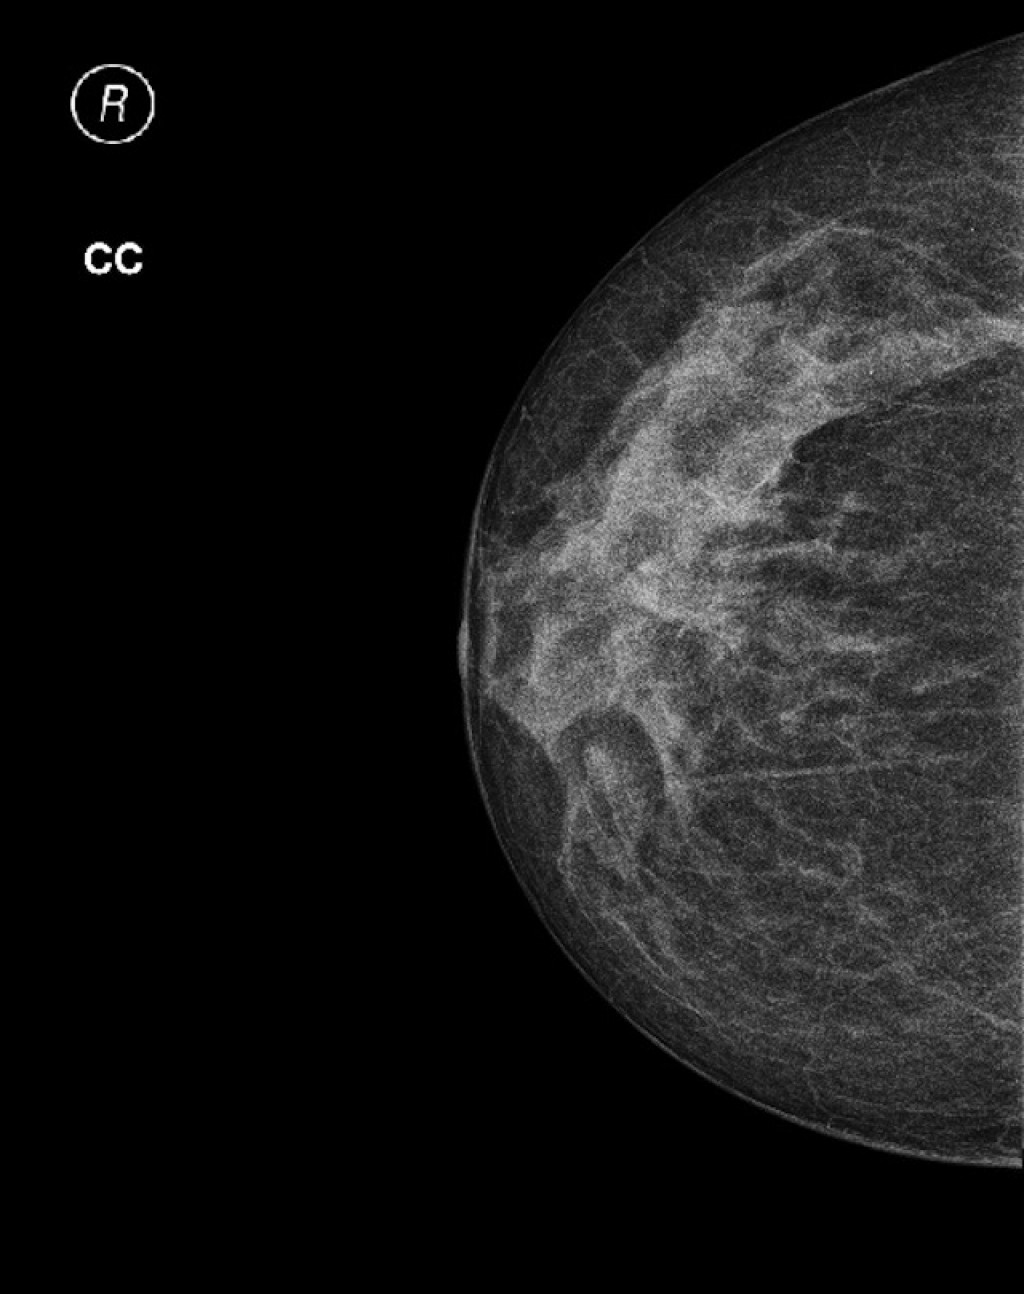

Фиброаденома молочной железы - доброкачественное образование, которое часто встречается у женщин. Оно может быть обнаружено при помощи различных методов диагностики, включая маммографию. Ниже представлены фотографии, помогающие понять, как выглядит данное заболевание.

Маммография и ее роль в диагностике фиброаденомы молочной железы

Маммография - это рентгенологическое исследование молочных желез. Оно позволяет выявить различные изменения в тканях, включая фиброаденому. На маммограммах можно увидеть структурные особенности опухоли и отследить ее динамику во времени.